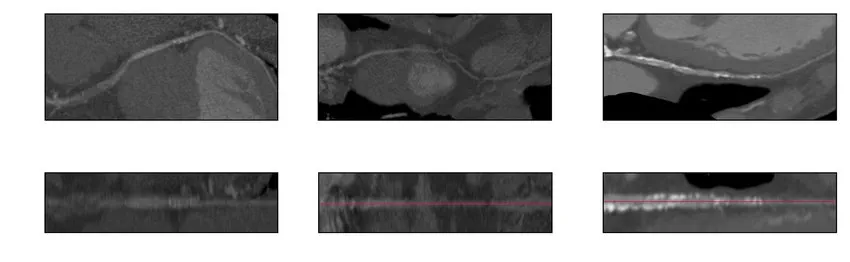

1. Curved multiplanar reformation (CPR) and stretched multiplanar reformation (sMPR) are commonly used to diagnose coronary disease. These techniques essentially stretch the 3D vessel along a plane into a straight line for easier interpretation of its structure and interior by eliminating other information from vast 3D voxels.

CPR and sMPR

Top: CPR, Bottom: sMPR